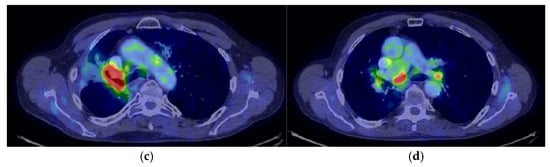

2. Case Presentation

2.3. Oncological Committee 07/25/2023 Recommended

- Consider rescue re-irradiation (SBRT), taking into account the current primary tumor dimensions of 24 × 34.2 mm on PET CT from 06/2023 and also the total dose previously administered (08–09/2020), the previously applied fractionation, the time between the two irradiations, the cellular repair time and the dose constraints for the organs at risk.

| 05.08–18.09.2020 | Palliative RTE (primary tumor + regional lymph node areas) | DT = 61.2 Gy |